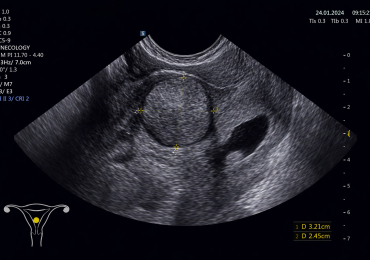

В своей практике доктор использует разнообразные методы диагностики, позволяющие точно и быстро оценить состояние здоровья пациенток. Она проводит осмотры, осуществляет кольпоскопию, выполняет лечебные процедуры и применяет малоинвазивные хирургические техники, что минимизирует риски и позволяет добиваться оптимальных результатов.